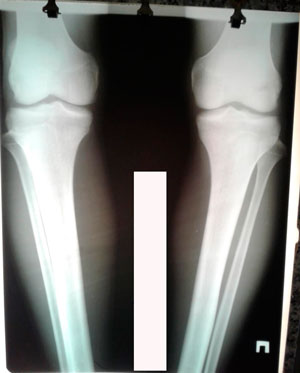

на фиксации

Вложения